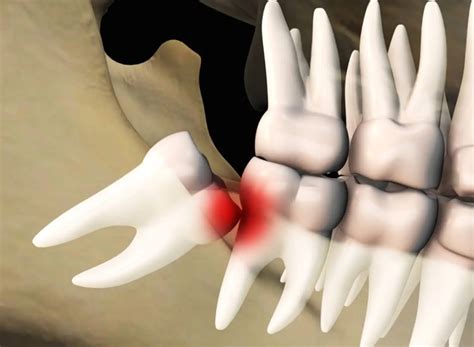

Diferentes posiciones de las muelas del juicio

La muela del juicio puede posicionarse de diversas maneras dentro de la mandíbula. Esta posición determinará la complejidad de su extracción y el tipo de molestia que genere. A continuación, se detallan las posiciones más frecuentes:

Posición Descripción

Mesioangular La muela está inclinada hacia adelante, presionando al segundo molar.

Vertical La muela está en posición correcta, pero no tiene espacio para salir.

Distoangular La muela está inclinada hacia la parte posterior de la boca.

Horizontal La muela crece de forma completamente horizontal, impactando contra el segundo molar.